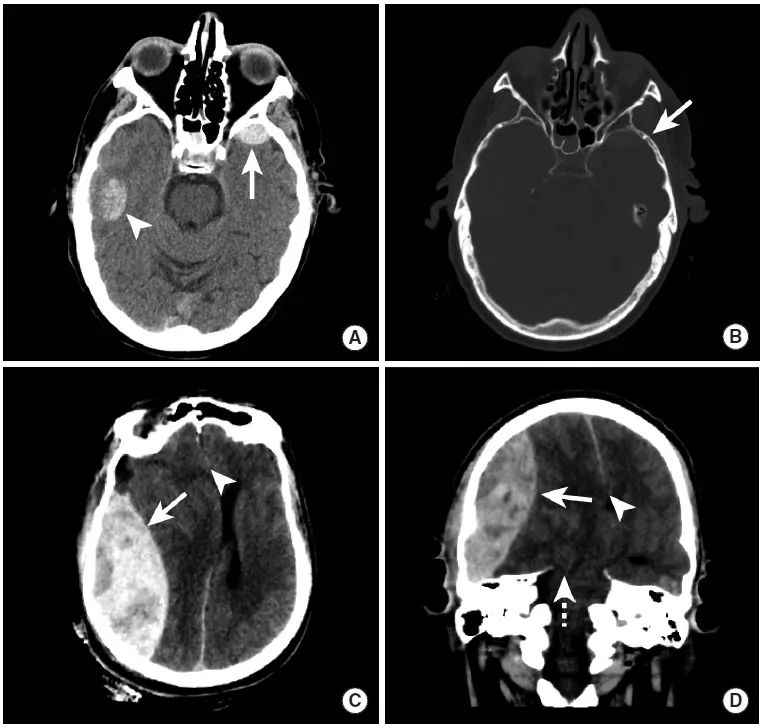

图1

本例为车祸导致的外伤性蛛网膜下腔出血。

图A:平扫CT显示脑沟内高密度影(长尾箭头),此外还可以看到左侧的硬膜下血肿(三角箭头)以及右顶骨处的帽状腱膜下血肿(虚线箭头)。

图B:MRI FLAIR序列同样可见脑沟内高信号,证实了蛛网膜下腔出血的存在,同时可见左侧硬膜下血肿和右侧帽状腱膜下血肿。

图C:GRE序列上,蛛网膜下腔出血和硬膜下血肿表现为低信号。